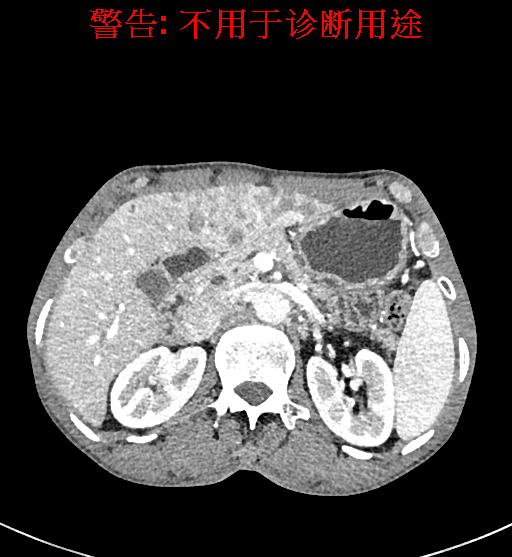

实验室检查: 血常规:WBC 4.89*109/L,RBC 3.64*1012/L, HB 119.00g/L, HCT 35.40%,PLT 123*109/L,RET% 0.48%, RET 0.017*1012/L, IRF 2.00%生化全套:ALT 56.00U/L AST 60.00U/L, LDH 312.00U/L TP 72.08g/L ALB 32.44g/L, GGT 101.00U/L,TBA 21.90umol/L,A/G 0.82,ADA 23.00U/L, PAB 94.20mg/L, CHE 5405.00U/L 肿瘤标志物:CEA 2.80ng/mL CA19-9 11.46U/ml 肝炎全套: HAV-IgM 0.21S/CO, HBcIgM 0.330S/CO, HCV-cAg 0.08S/CO, HEV-IgM 0.03S/CO, HBeAg 6.000S/CO 诊疗过程: CT结果输入海信CAS系统后行3D重建及手术规划后,于2018-5-17局麻下行“经皮肝动脉造影术+肝动脉化疗栓塞术”手术治疗 术前三维重建及手术方案设计: 将0.625mm双源薄层CT资料的静脉期和动脉期Dicom格式文件导入海信CAS系统。 通过调节窗宽窗位调整CT序号,对肿瘤,肝实质,胆囊,下腔静脉,肿瘤,肝动脉、门静脉及肝静脉等进行三维重建;系统自动计算肿瘤体积和肝脏体积。肝脏体积为1563ml,肿瘤体积为537.6ml,通过比对50-60岁正常肝脏体积为1343.28±246.69ml。 手术步骤: 常规准备后,患者仰卧于DSA手术床。常规双侧股动脉区域消毒,铺巾。2%利多卡因局部麻醉右侧股动脉区成功后,应用Seldinger技术穿刺右侧股动脉,置入5F动脉鞘。送5F 肝导管至腹腔干、肝动脉造影,肝区可见团块状及多发结节状肿瘤染色、侵犯门静脉左支。静脉推注维瑞特5mg后,透视下将微导管分别超选择至各支肿瘤供血动脉内,应用雷替曲塞4mg+奥沙利铂50mg+表柔比星20mg +LP 10ml的混合液及适量350-560um明胶海绵进行栓塞,后造影示栓塞适量,退出导管、血管鞘,局部压迫10min,加压包扎。患者术中未诉不适,术后平车安返病房。随访情况: 患者术后3月复查上腹CT示肝左叶病变活性残留,腹腔内、腹膜后多发略大淋巴结,部分较前略减小,今患者为求进一步诊治,与我院再次行“肝动脉造影+经导管肝动脉栓塞术”,术后2周无明显不适 术前CT检查:动脉期

平衡期